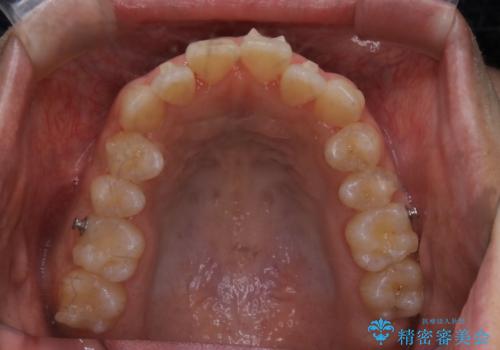

オープンバイト(開咬)を非抜歯インビザラインで治す

- 上下のがたつきを気にされてご相談にいらした患者さまです。

症状としてはオープンバイト(開咬)があり、舌癖も見られました。

オープンバイトの方への治療は、通常抜歯を行いワイヤーによる矯正治療を行うことが多いですが、今回はインビザラインの特性を生かし、非抜歯にて綺麗な歯並びを作ることが出来ました。